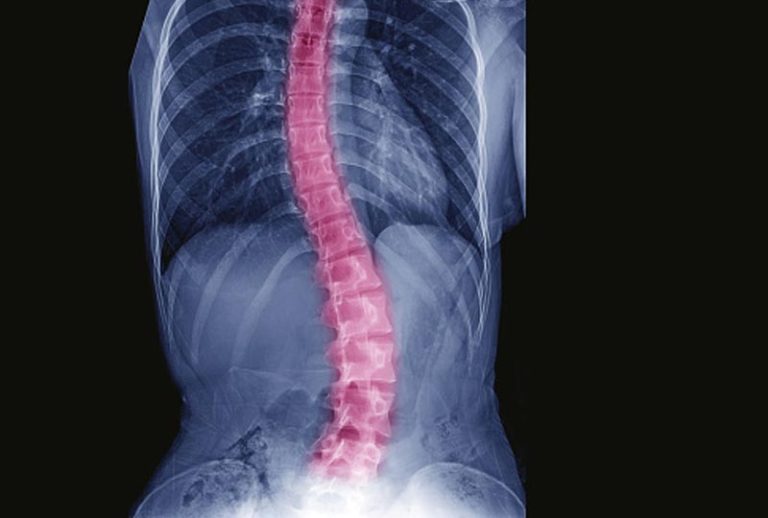

Prevenir lesiones en el running

Lesiones en el running Ante la pregunta de un periodista acerca del secreto de su buen estado de salud y de su longevidad, Winston Churchill